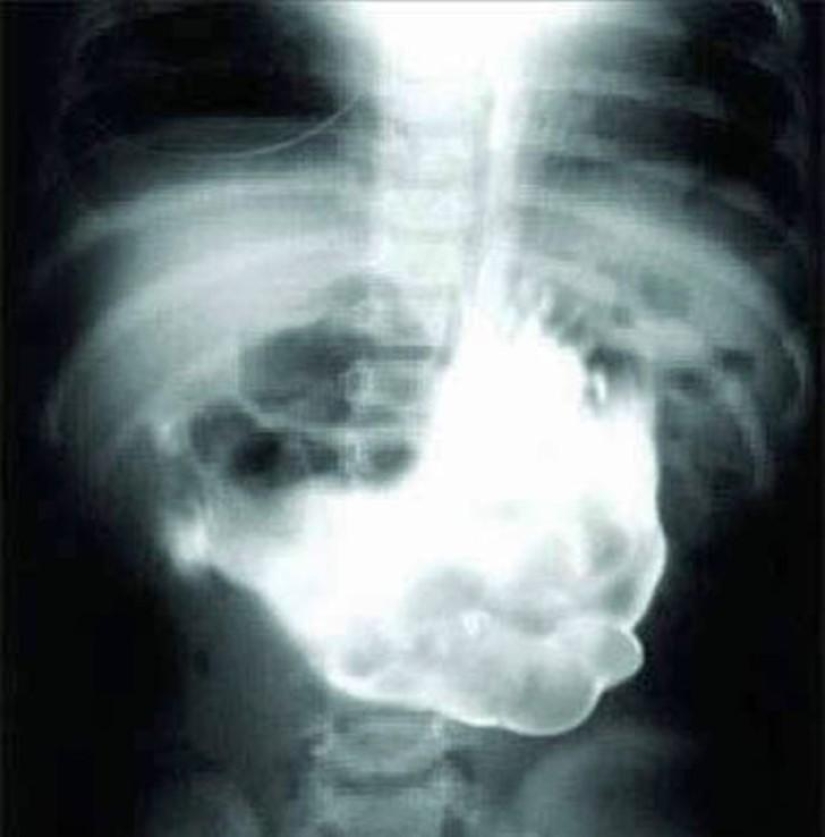

Anguila viva.